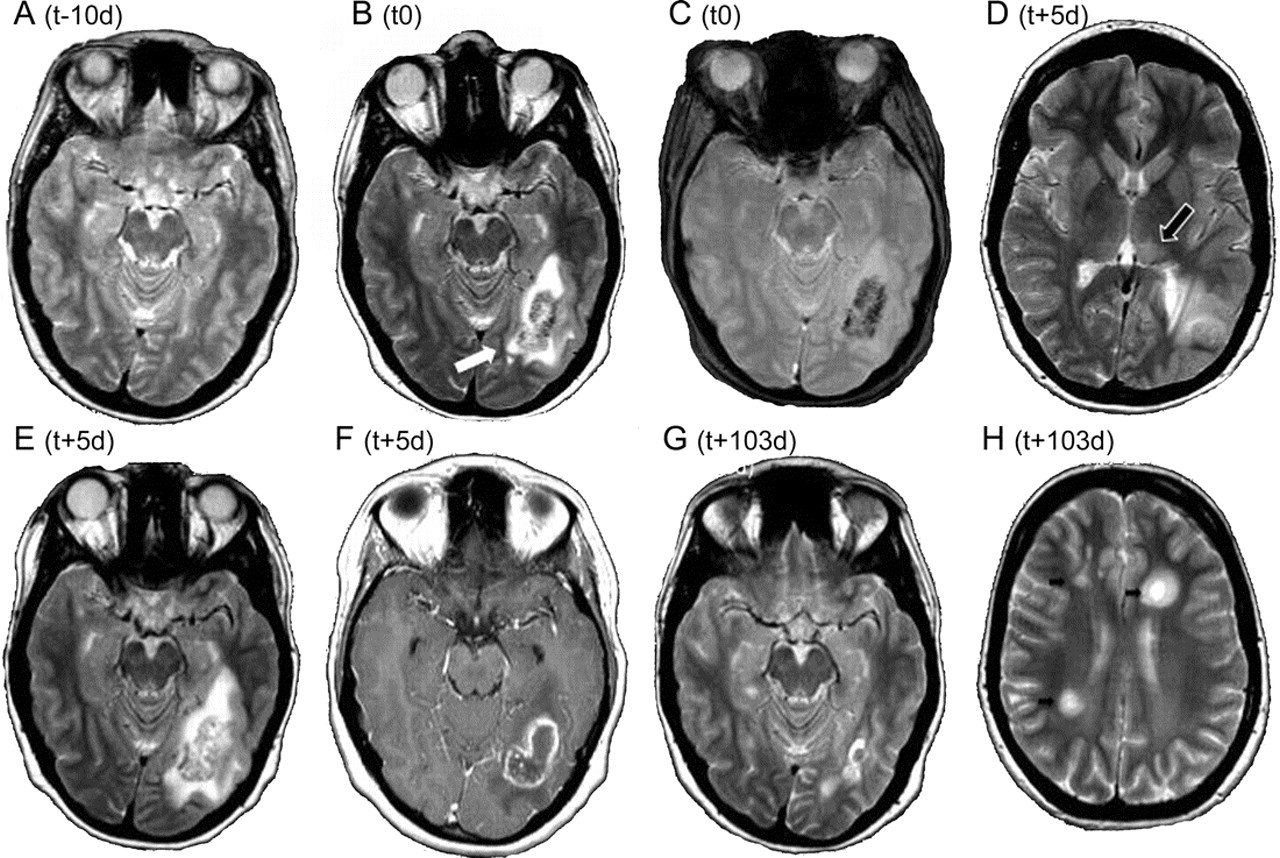

图一系列选定的核磁共振扫描

括号表示在入院时间。(A, t2加权[T2W])常规颅MRI出现临床症状前10天没有异常。承认(B, T2W)相应的图像显示hypointense非齐次结构有着明显的病灶周边水肿(白色箭头)在左颞顶白质与易感性工件对应于出血性转换(C, T2 * W)。五天出现症状后,一个新的T2W hyperintense病变在左丘脑枕是注意到(D, T2W,黑色箭头)。左颞顶病变的大小和水肿的进展(E, T2W)和强perilesional增强钆注射后观察到的(F, T1W)。入院后103天,病灶周边大脑的损伤是有缺陷的,没有反应实质(G, T2W)。新多发性硬化症可疑病变(H, T2W,小箭头)出现在皮层下白质。这些都是钆增强(没有显示)。

在重复cMRIs在随后的15周,病变大小和水肿下降(图G),但新的临床无症状t2加权hyperintense病变在左丘脑枕(图D)、juxtacortical白质和脊髓出现了。因为越来越多的证据对感染性原因,抗生素被中断(伏立康唑10天,meropenem 42天,cefpodoxime 14天)没有恶化。

临床过程是由一系列复杂的复杂部分发作期间应对levetiracetam第一周(2 g)。她的条件逐渐改善,但轻微的遗忘性失语持久化。后续继续展现新Gd-enhancing亚临床病变的MRI(例如,图中,H)。Daclizumab治疗(1毫克/公斤体重每4周)开始。任何时候都是类固醇。